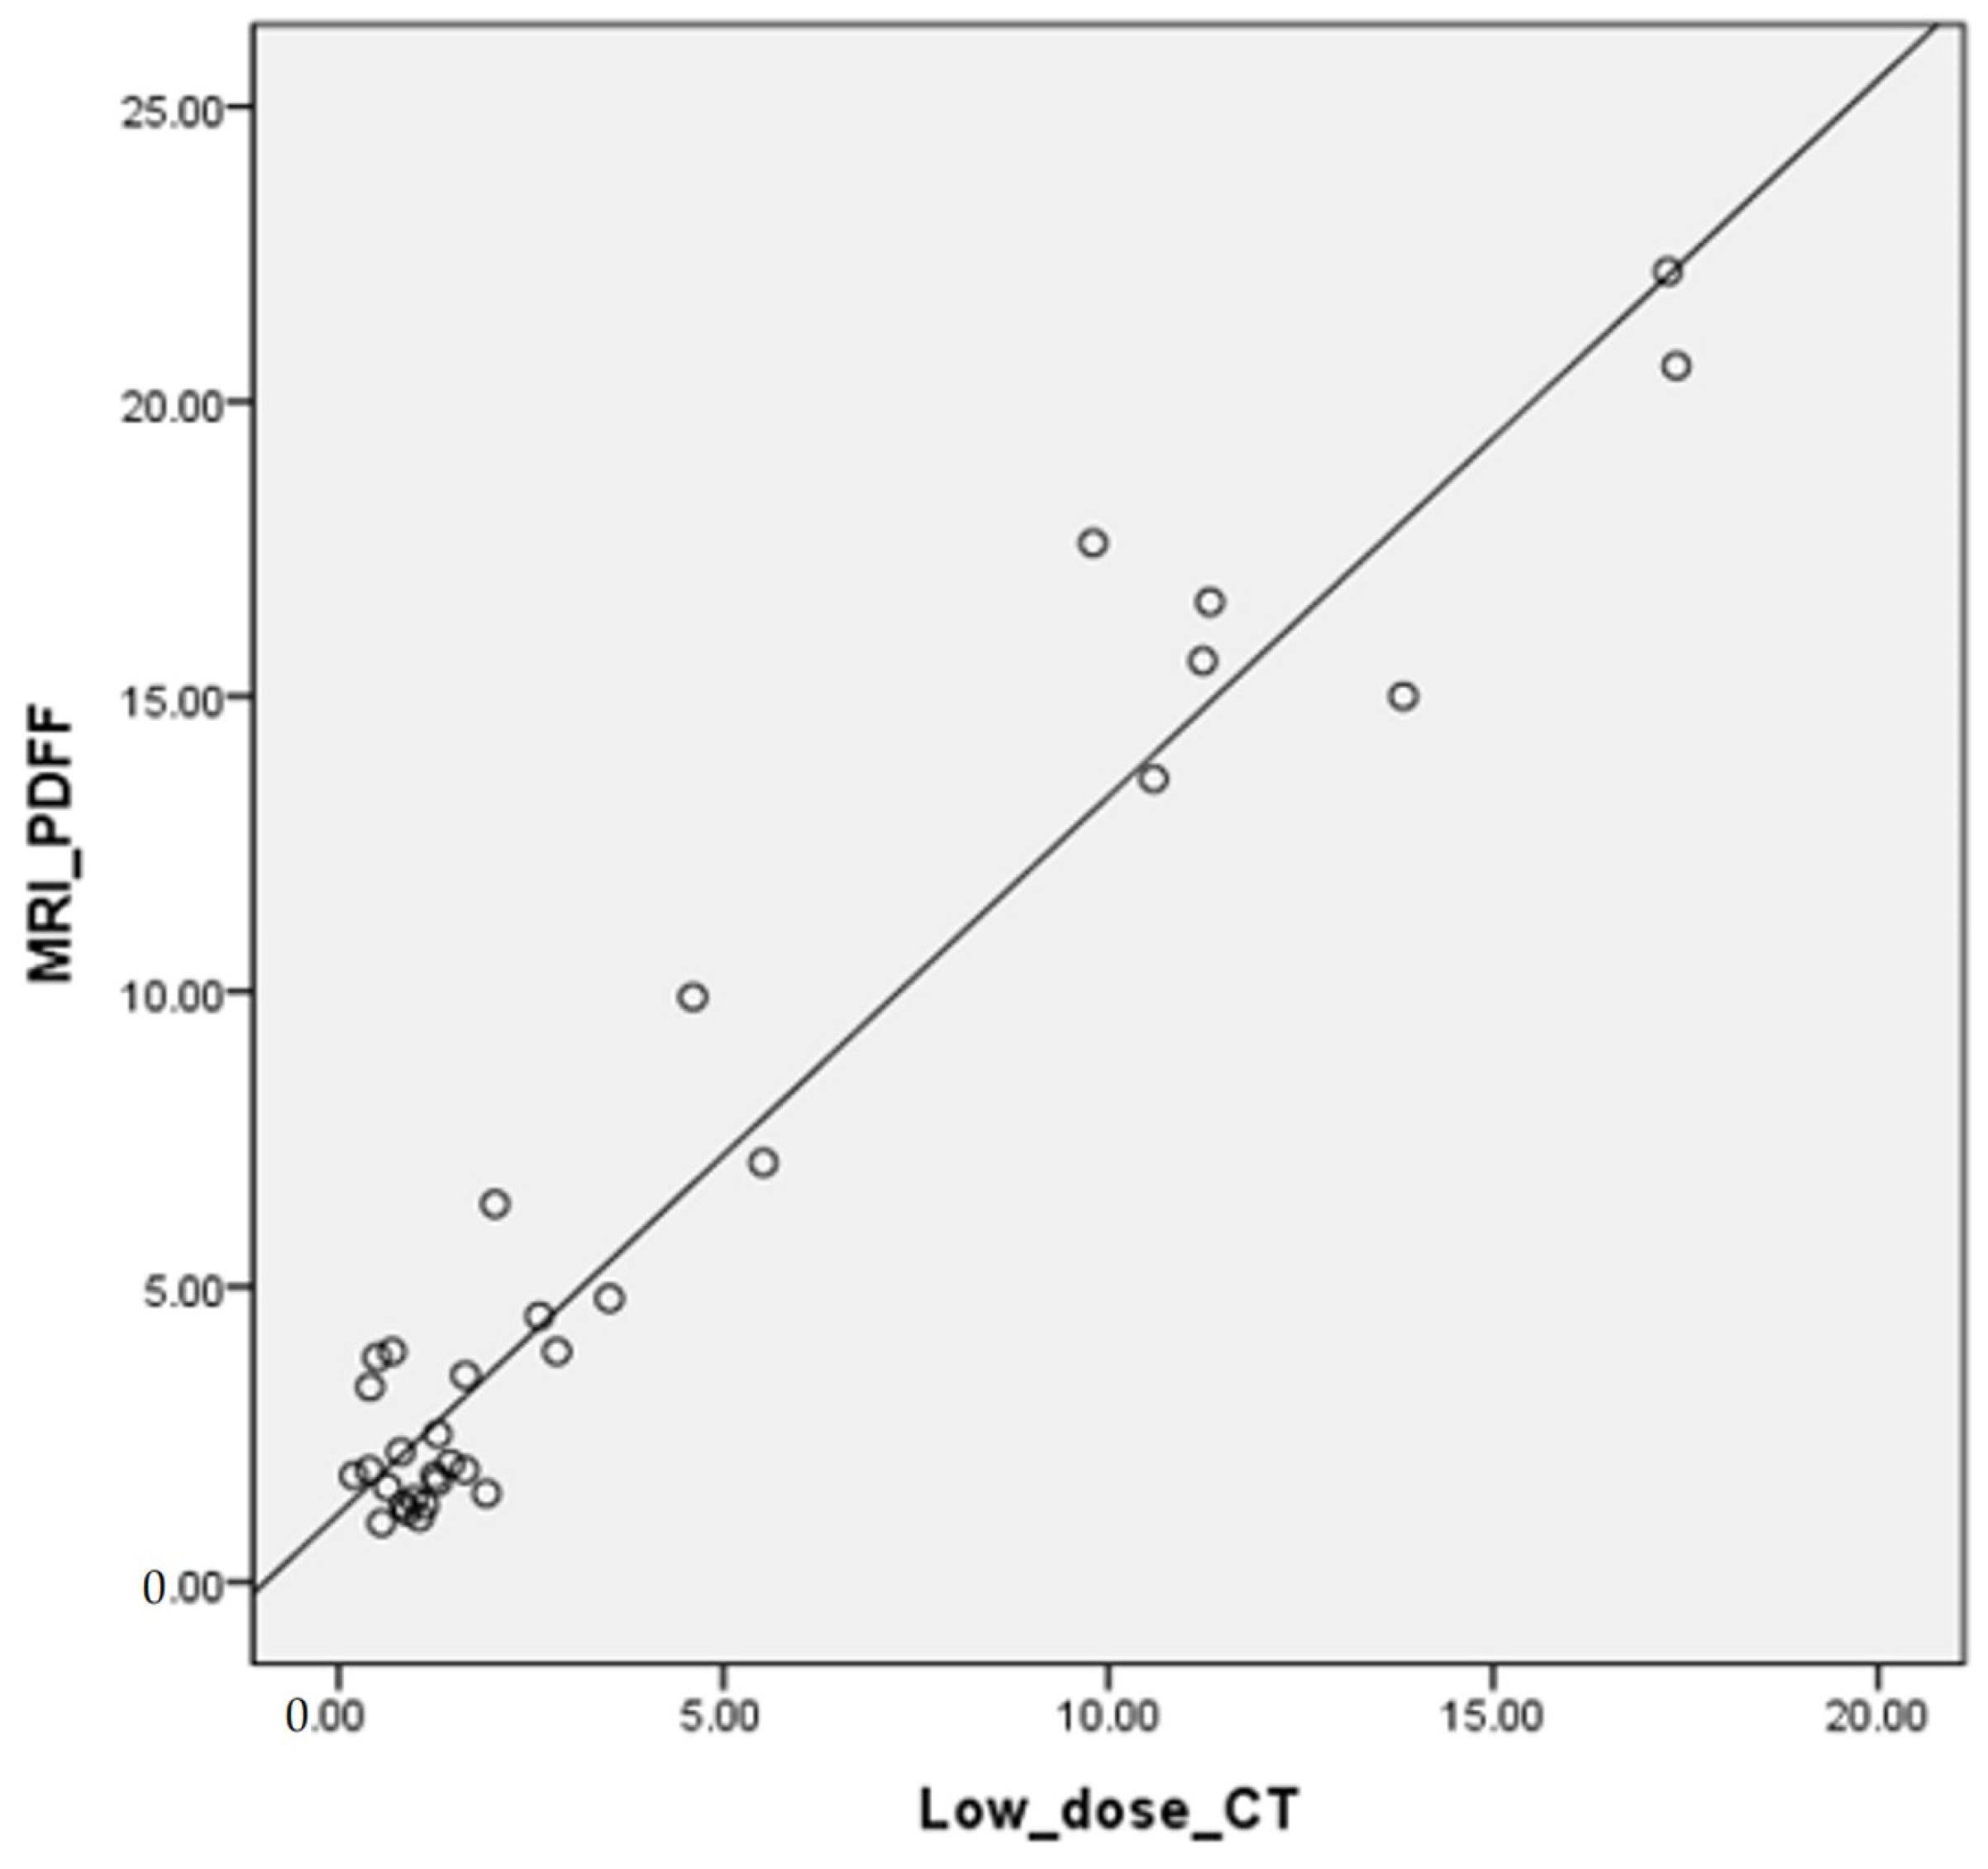

3.4. Correlation of FVF with MRI-PDFF